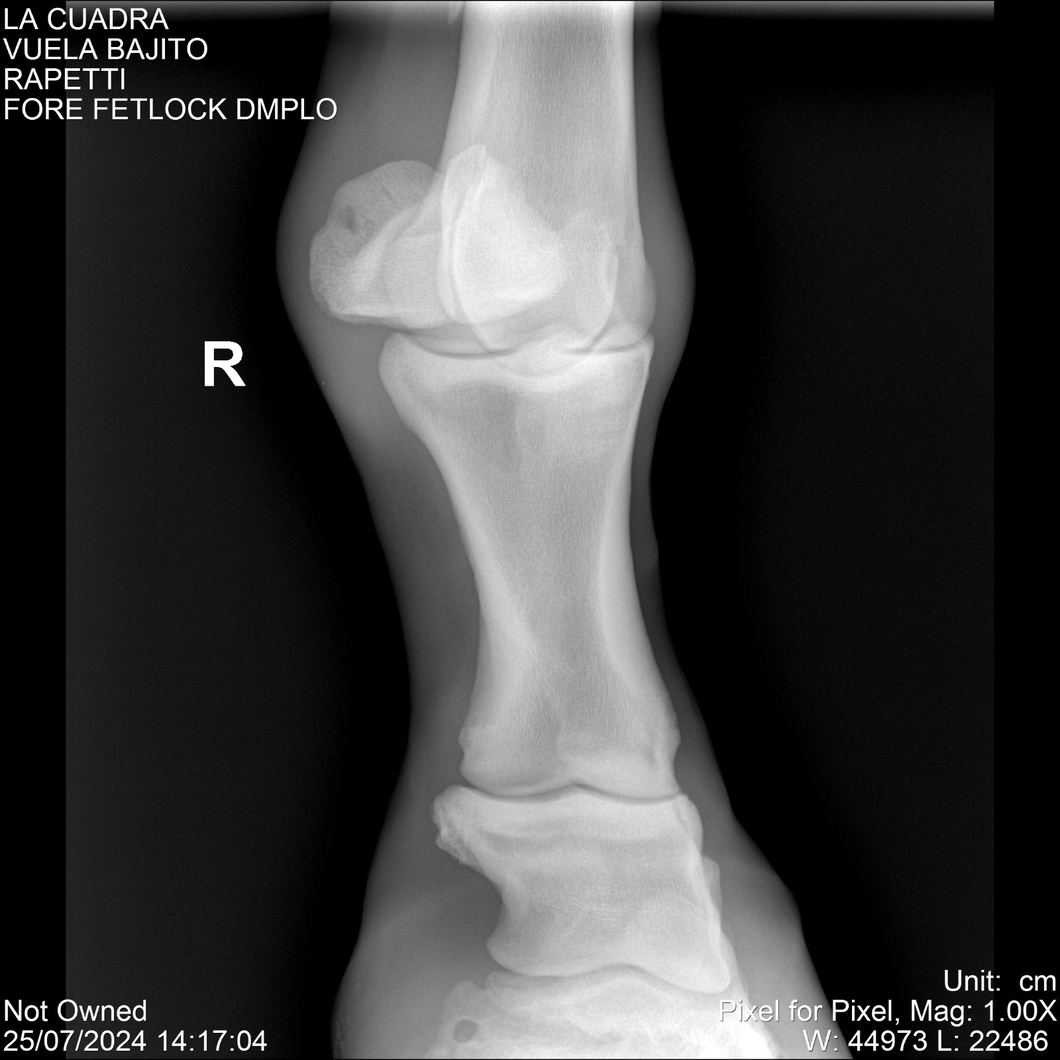

LOTE 16, VUELA BAJITO Lote Anterior Volver al remate Lote Siguiente Ficha Contacto Montevideo - Ficha del Lote Identificador: #284451 Categoría: Yeguarizos Montevideo - 77 Visualizaciones ClicData Contacto Empresa: Abelenda N. R., Walter Hugo Nombre*: Teléfono* : E-mail* : Mensaje Enviar Registrese gratis Este contenido Exclusivo está disponible sólo para usuarios registrados Ingresar